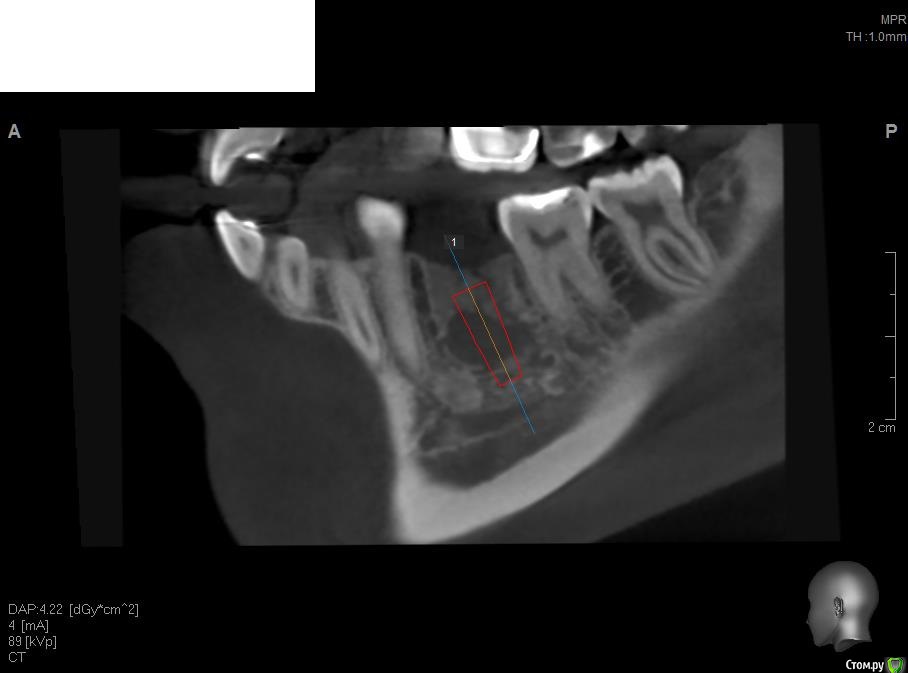

Кариес+ Опубликовано 18 октября, 2015 Поделиться Опубликовано 18 октября, 2015 Зравствуйте коллеги имею не большой опыт в имплантации есть некоторые вопросы. планируется операция в области 4.6 , судя по кт есть небольшое просветление у вершины гребня , будет ли там кость или готовиться к нкр? Ссылка на комментарий

Aquarius Опубликовано 18 октября, 2015 Поделиться Опубликовано 18 октября, 2015 Срез надо по ширине поменьше, но похоже,что не надо никакой НКР, особенно в свете последних трендов 1 Ссылка на комментарий

Aquarius Опубликовано 18 октября, 2015 Поделиться Опубликовано 18 октября, 2015 Там по середине у Вас какая-то каверна рисуется непонятная, но в общем даже если не хватит кости, добавить коллагена с бугра при оголении импланта ( что маловероятно в Вашем случае) и спать спокойно Ссылка на комментарий